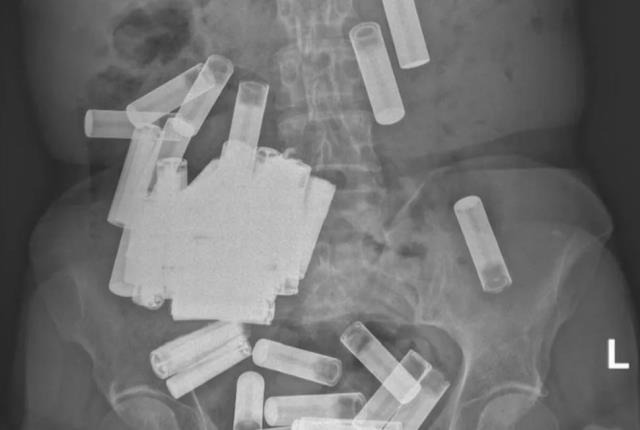

Nezarettv.Az xəbər verir ki, müxtəlif şikayətlərlə xəstəxanaya müraciət edən yaşlı qadını müayinə edən həkimlər onun müxtəlif orqanlarında 55 batareya aşkar ediblər.

Həkimlər batareyaların sayını dəqiqləşdirmək üçün qadını bir neçə dəfə müayinə ediblər. Batareyalar qadının mədəsində, bağırsaqlarında və digər orqanlarında ilişib qalıb. Müxtəlif üsullardan istifadə edilərək təkcə 4 batareyanı çıxartmaq mümkün olub. Digər batareyaların çıxarılması üçün cərrahlar hərəkətə keçiblər. Qadının səhhəti üçün təhlükə olmadığı bildirilib. Hadisənin səbəbləri araşdırılır.